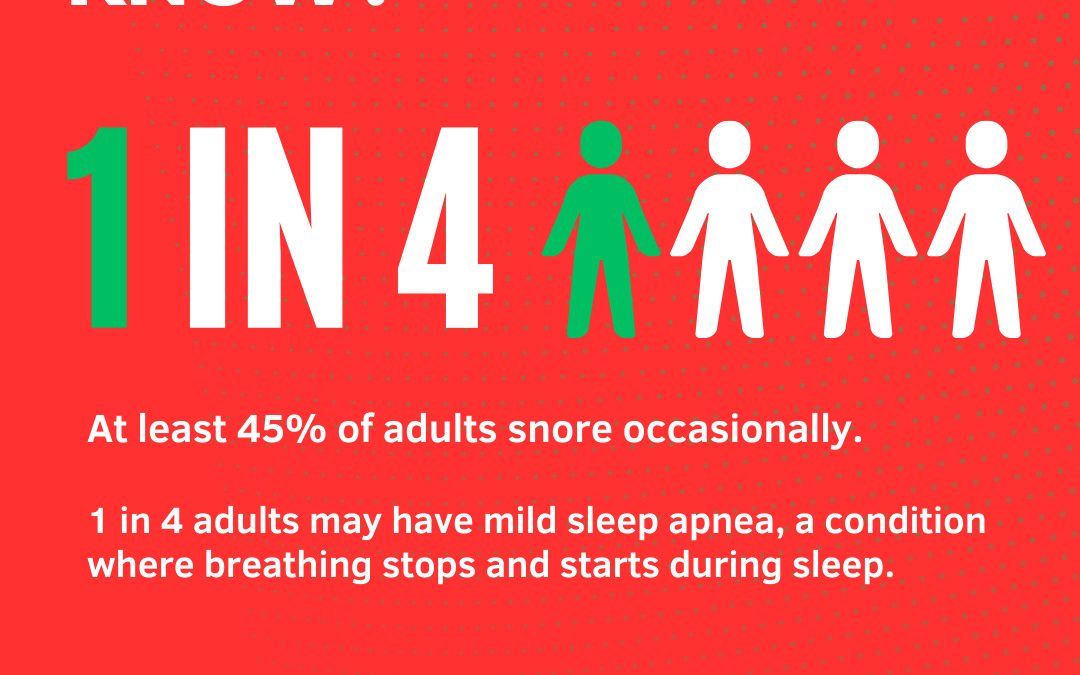

SLEEP SOUNDLY THIS HOLIDAY SEASON: TIPS FOR SNORE-FREE NIGHTS

SLEEP SOUNDLY THIS HOLIDAY SEASON: TIPS FOR SNORE-FREE NIGHTS The holidays should be filled with Silent Nights and Joyful Days,but snoring can put a damper on the cheer! We hope thefestive tips keep the nights quiet and restful for everyone.Wishing you a Merry Christmas and a Silent Night